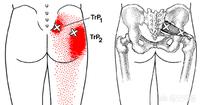

2.臀中肌综合征

夜间侧卧可能疼痛 , 疼痛部位也是臀部外侧腿外侧 , 早晨起床的时候是下地站立的时候疼痛 , 活动一会减轻 。